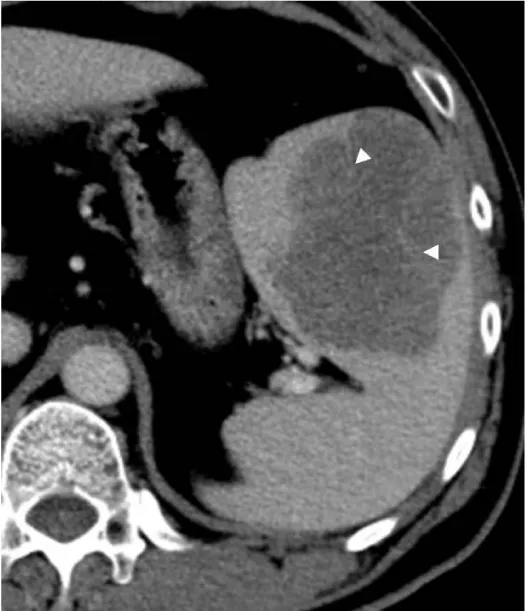

Solitary well-circumscribed masses were detected in all the five patients by ultrasound. One mass was of hypoecho, while the remaining masses were of hyperecho with posterior enhancement (Figure 1A). The maximum diameter ranged from 3.0 cm to 9.0 cm. At CT scanning, two masses appeared as hypodense (Figure 1B) and one was isodense (Figure 2A) to the normal spleenic parenchyma. In the two patients who received MR imaging, masses were isointensity at T1 weighted images (Figure 3A) and hypointensity with scattered sign void spots at T2 weighted images (Figure 3B). After intravenous injection of the contrast materials, all the five masses presented circle enhancement at arterial phase (Figure 3C and Figure 4A), while peripheral enhanced node was noted in one mass (Figure 2B). The circle enhancement persisted and radical line enhancement were observed at portal vein phase in 3 cases (Figure 1C) and progressive filling in was seen in two cases (Figure 2C). At delay phase of MR imaging, one lesion showed obvious enhancement with stellate low signal scar in the center comparing with surrounding splenic parenchyma (Figure 3D), while the other demonstrated central and circle enhancement to form a spoke-like appearance (Figure 4B). At delay enhanced CT scanning, two masses were isoattenuation to the surrounding splenic parenchyma (Figure 2D) and one lesion kept as hypoattenuation but with radial enhanced lines and enhanced circle to form a spoke-like appearance.

At pathological examination, all the masses were well demarcated on gross cut surface. A central stellate scar with peripheral interspersed dark brown nodules and the whitish intervening fibrous bands was noted to form spoke-like appearance (Figure 3E), which was well correlated with CT and MR imaging findings at enhancement. Microscopically, these angiomatoid nodules were surrounded by dense concentric collagen fibrous stroma and dispersed stromal cells with oval-to-spindle nuclei and scanty cytoplasm (Figure 3F). The abunden fibrous stroma may result in hypointensity at T2 weighted MR images. Hemosiderin was noted in the angiomatoid nodules (Figure 3G), which might contributed to signal void at T2 weighted MR images.

It usually affects middle-aged adults [6] and it is commonly found incidentally on radiographic imaging, or during operation for an unrelated condition. In present series, the patients are middle-aged adults without any related symptoms and the lesions were detected incidentally at routine ultrasound of health examinations. On ultrasound, manifestations of SANTs are vary widely from heterogeneous echo-texture with hyperechogenic, hypoechogenic, or isoechogenic appearing lesions, which are unspecific [7,8]. CT and MRI can show some characteristic features of SANTs, which include a solitary well demarcated mass with early peripheral enhancemant with radiating lines and progressive enhancement at the delay phase, and hypointens at T2 weighted MR images [2,3,5,9-13]. These features reflect the underlying pathological changes of scattered angiomatoid nodules separated and surrounded by sclerotic fibrotic stroma [10]. In present series, we also observed these characteristic features with well correlation to pathological findings. Circle and spoke-like enhancement can be contributed to fibrotic stroma surrounding and separating the angiomatoid nodules. The sclerotic fibrotic stroma may also result in isodense on CT, isointensity on T1 weighted images and hypointensity on T2 weighted images of MR imaging. The signal void spots at T2 weighted MR images have not been described at other literatures and may be contributed to hemosiderin deposition due to magnetic susceptibilty artifact.